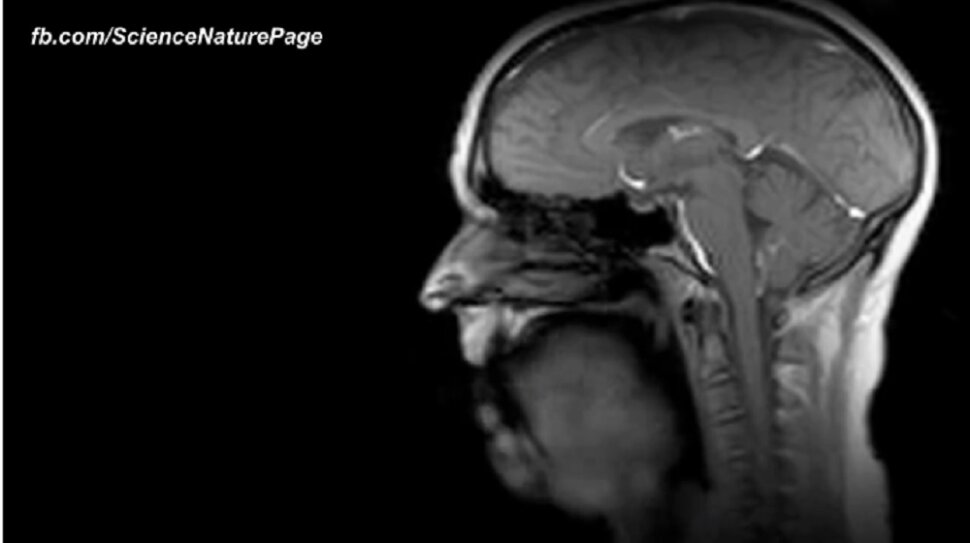

Znamo kako izgledaju organi, no jeste ikad vidjeli svoje organe i njihove funkcije u MRI snimci ili čak u X-ray izdanju?

Pogledajte kako izgleda kucanje vašeg srca, što se događa kada gutate, kako vaša usna šupljina izgleda u MRI snimci dok pjevate, ili čak kako se blizanci 'igraju' još uvijek u majčinom trbuhu.